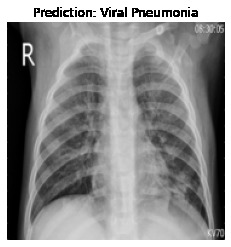

Currently, there is an urgent need for efficient tools to assess the diagnosis of COVID-19 patients. In this project, we propose a constructive solution for detecting and labeling infected tissues on CT lung images of such patients. To cut down false positives our model is trained on 4 types of lung CT images : COVID, Viral Pneumonia, Lung Opacity and normal images to get the best possible results with highest accuracy.

We built it using Tensorflow 2.x using Python. We have developed a Convolutional Neural Network model with an average accuracy of more than 85%.

We experimented with numerous numbers of model and came up with top 5 models to represent our dataset. The challenge that we faced was finding the best dataset for training our model on. The other challenge we ran into was, our model's low accuracy and high loss. We worked on our model continously and fine tuned it to reach a very good accuracy.

We are proud that among the top 5 models, one of our models achieved 88.8% accuracy with very low loss.